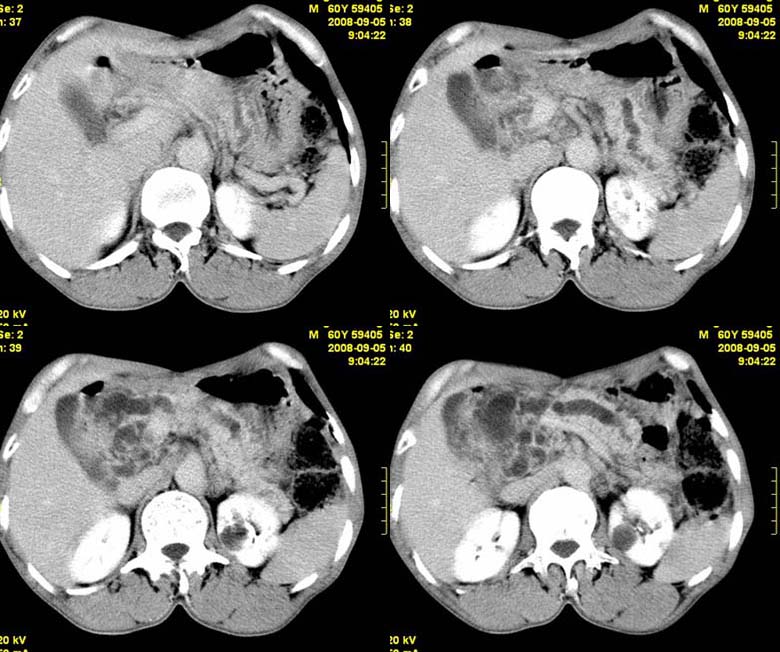

标题: CT15580:M60Y,胰腺病变,平扫+增强 [打印本页]

标题: CT15580:M60Y,胰腺病变,平扫+增强

患者,男, 60,既往有间歇腹痛病史多年,现右上腹痛,加重一月,伴右后背部疼痛,无黄疸,无发热。

胰头区增大,胰管明显扩张,不均匀强化,且与 周围结构不清,后背疼痛,考虑为胰腺头部胰腺癌。

胰头区增大,胰管明显扩张,不均匀强化,且与 周围结构不清,后背疼痛,考虑为胰腺头部胰腺癌。

同意胰头部囊腺癌

胰头囊样增大不均匀强化,腺管扩张。结合病史首诊慢性胰腺炎、假性囊肿